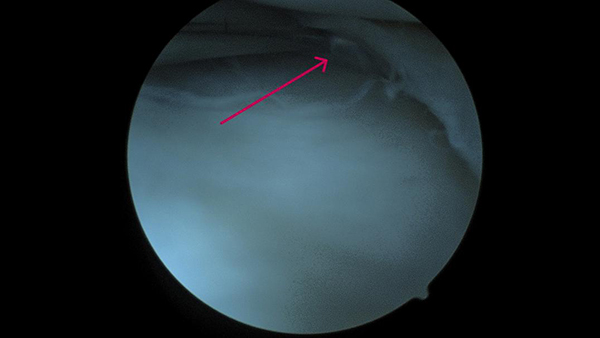

▲术中发现水平撕裂的半月板(红色箭头所示)